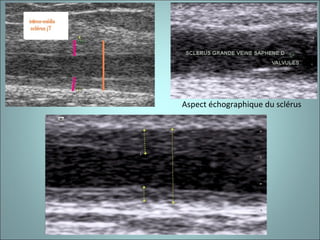

Aspect échographique du sclérus

SCLERUS : épaisseur IM  et halo claire en cocarde

THROMBOSE VEINEUSE (TVS et TVP) : -  Absence d’élévation de l’intima-média - Absence de halo clair péri-veineux en cocarde - Thrombus échogène convexe - Biologie modifiée (D-dimères élevés).

SCLERUS : épaisseurIM et halo claire en cocarde